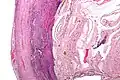

Even for clinically certain appendicitis, routine histopathology examination of appendectomy specimens is of value for identifying unsuspected pathologies requiring further postoperative management.[75] No sign of appendicitis in specimens, negative appendectomy, varies but has been estimated to occur in 13% of specimens.[76] Notably, appendix cancer is found incidentally in about 1% of appendectomy specimens.[77][78]

Pathology diagnosis of appendicitis can be made by detecting a neutrophilic infiltrate of the muscularis propria.

Periappendicitis (inflammation of tissues around the appendix) is often found in conjunction with other abdominal pathology.[79]

-

Micrograph of appendicitis and periappendicitis. H&E stain. -

Micrograph of appendicitis showing neutrophils in the muscularis propria. H&E stain. -

Acute suppurative appendicitis with perforation (at right). H&E stain.